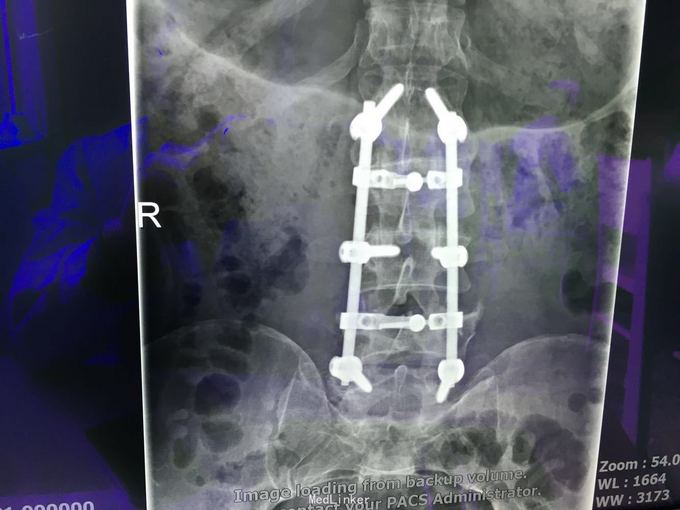

查体:左肾区叩痛,无皮肤隆起,未扪及肿块;腰椎压痛,活动受限,双下肢感觉存在,右小腿石膏托外固定,有踝关节明显肿胀,局部压痛活动受限,指端感觉血运可。 CT及X片:L2、L4椎体爆裂性骨折,L1-L4左侧横突骨折,右坐骨支骨折,右侧胫骨内、后及右侧腓骨外踝骨折,右足第1-4跖骨向外侧脱位及半脱位,伴近端斯脱性骨折。左肾挫裂伤,左肾重度积水,左肾周血肿。

诊断:右足lisfrance损伤,左肾挫裂伤;左肾周血肿,左侧输尿管结石伴左肾重度积水,L2、L4椎体骨折,L1-L4左侧横突骨折,右侧坐骨支骨折,右三踝骨折,全身多处皮肤软组织挫伤 处理:急诊行左肾探查,左肾切除术,择期行经后路腰2、4椎体骨折切开复位、椎公根螺钉内固定术+右内、外踝骨折切开复位内固定术,择期行右足lisfrance关节复位克氏针内固定术。